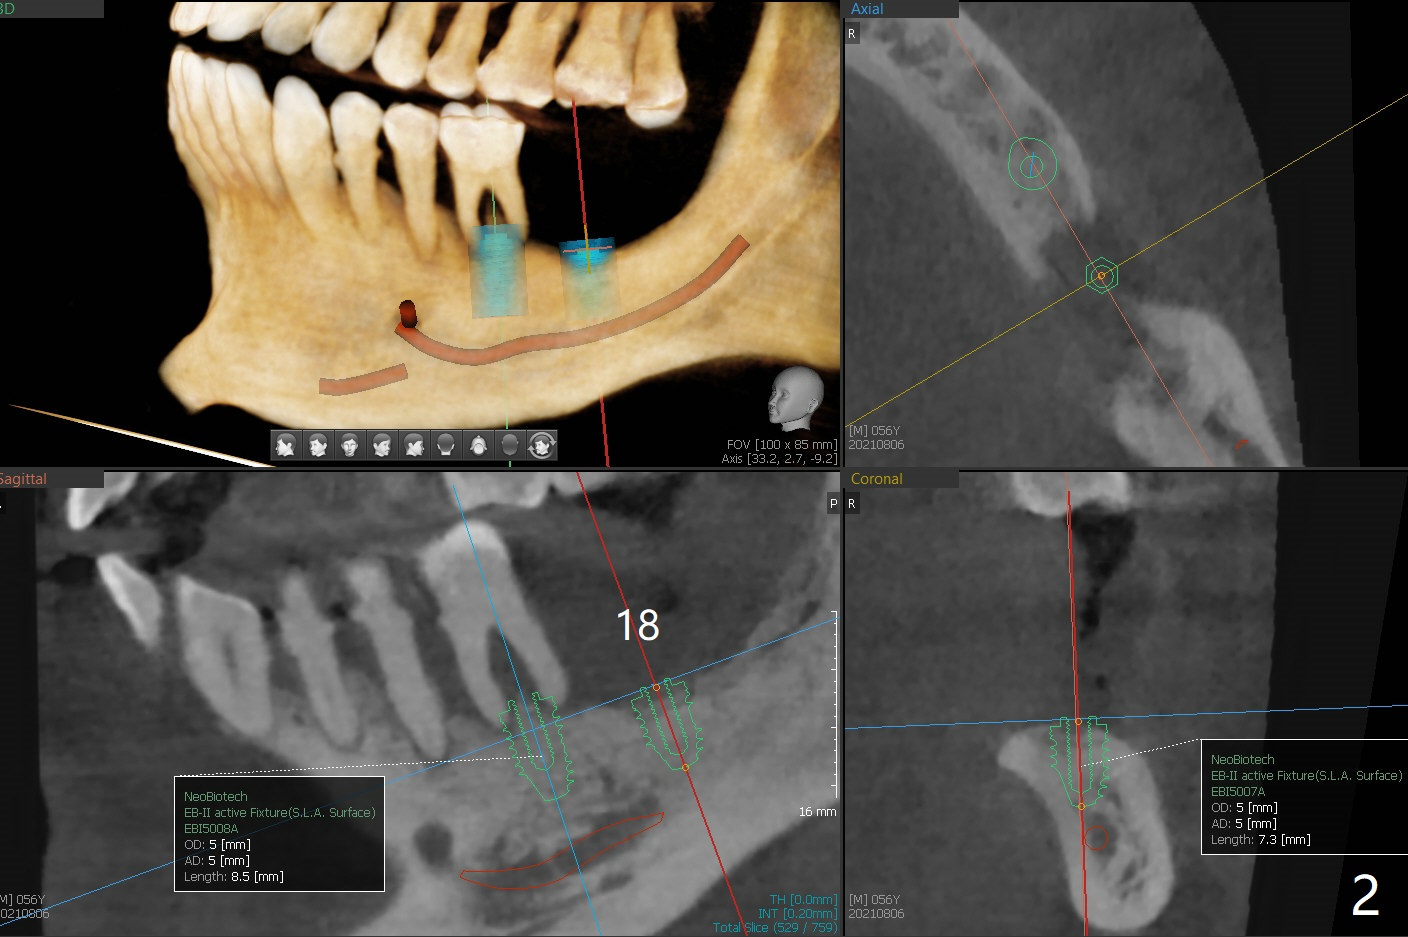

56岁男几十年拒绝牙周炎治疗,也不愿意拔除所有牙齿做全口植牙修复。17,18号牙自行脱落,现在要求拔除16,19;18,19种植(图一),后者牙龈厚(双箭头),但是18号牙骨质高度不足(图二),勉强植入5x7.3毫米植体。15,16骨质吸收严重(图三),16,19拔除,局部深洗后(图四:黑色),为了延长15号牙使用期,16号牙牙槽窝植骨(图五:红色)。19号牙种植徒手,因为邻牙(包括20,21号牙))松动,做导板不准确,钻洞使用环形钻头(图六),保留骨塞(bone plug),用于18号牙骨质高度骨块移植。19号牙拔除后,往远中18牙位做潜行分离(图七:黑色)。19种植(绿色),基台(粉红色),骨粉(圆圈),临时牙冠(白色),16号牙粘性骨粉植骨(红色),PRF,Cytoplast覆盖(白线),缝合。从19号牙钻洞取来的骨塞,塞入18号牙潜行分离处(图八);利用临时牙冠和22号牙以及钢丝,树脂固定20,21号牙(蓝色),并且降低咬合(*)。最后,用螺钉固定骨塞(图九:深蓝色)。